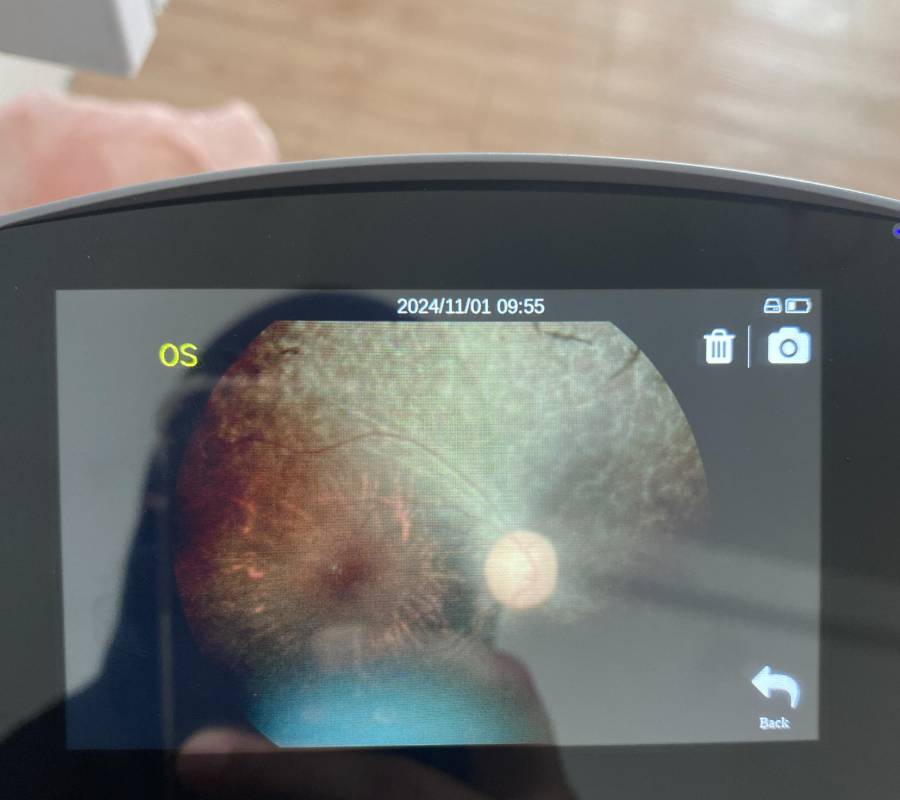

Pemeriksaan menyeluruh ke atas bahagian hadapan (anterior) dan belakang (posterior) mata—termasuk kornea, kanta, iris, retina serta saraf optik.